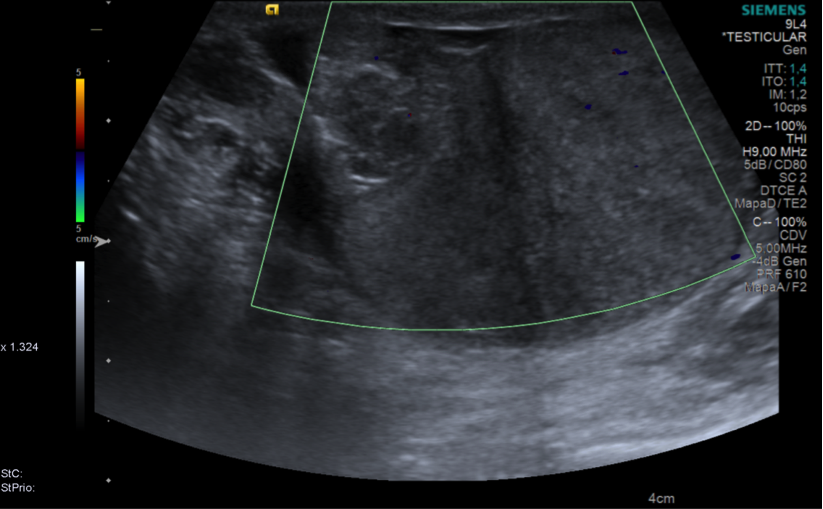

Realizamos ecografía doppler de testículo derecho en la que observamos testículo con ecoestructura heterogénea, con áreas hipoecoicas y ausencia de señal de flujo Doppler, compatible con torsión aguda, identifacando cordón espermático torsionado 360º.

Ante los hallazgos visualizados en la ecografía doppler y la nula viabilidad del testículo se realizó orquiectomía derecha y orquidopexia izquierda.